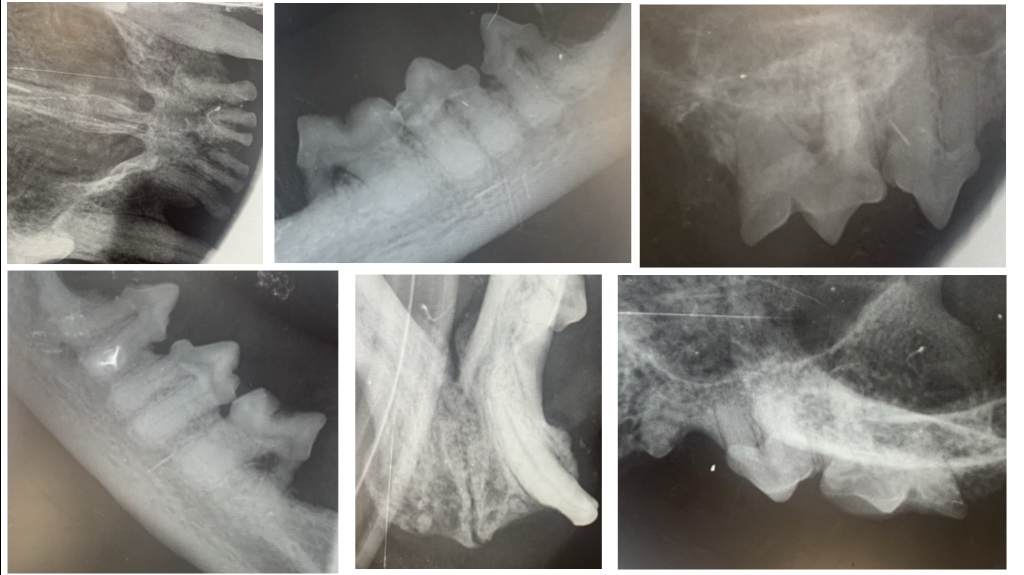

Лечение. Выполнены тотальное удаление зубов под контролем рентгенографии и альвеолопластика. Проведены кюретаж лунок и наложение швов (фото 4, 5).

Лечение. Проведены тотальное удаление зубов под рентгенологическим контролем, альвеолопластика, кюретаж и наложение швов (фото 10, 11).